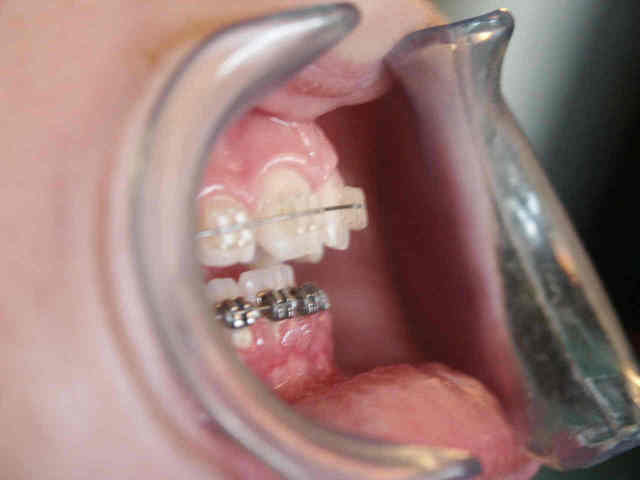

Collage bas fait presque 3 mois apres le haut, avec des elastiques verticaux pendant 3 semaines seulement. Et voici les photos, la suite je vous en passe car il s'agit de simple finition.

Les ponits forts dans cette reeducation sont: maitriser la respiration, reformer le maxillaire, une cooperation extra et une simplicite du system utilise. Merci pour votre attention et a la prochaine... Bonne annee 2007 a tous

P.S. photos au moment du collage bas